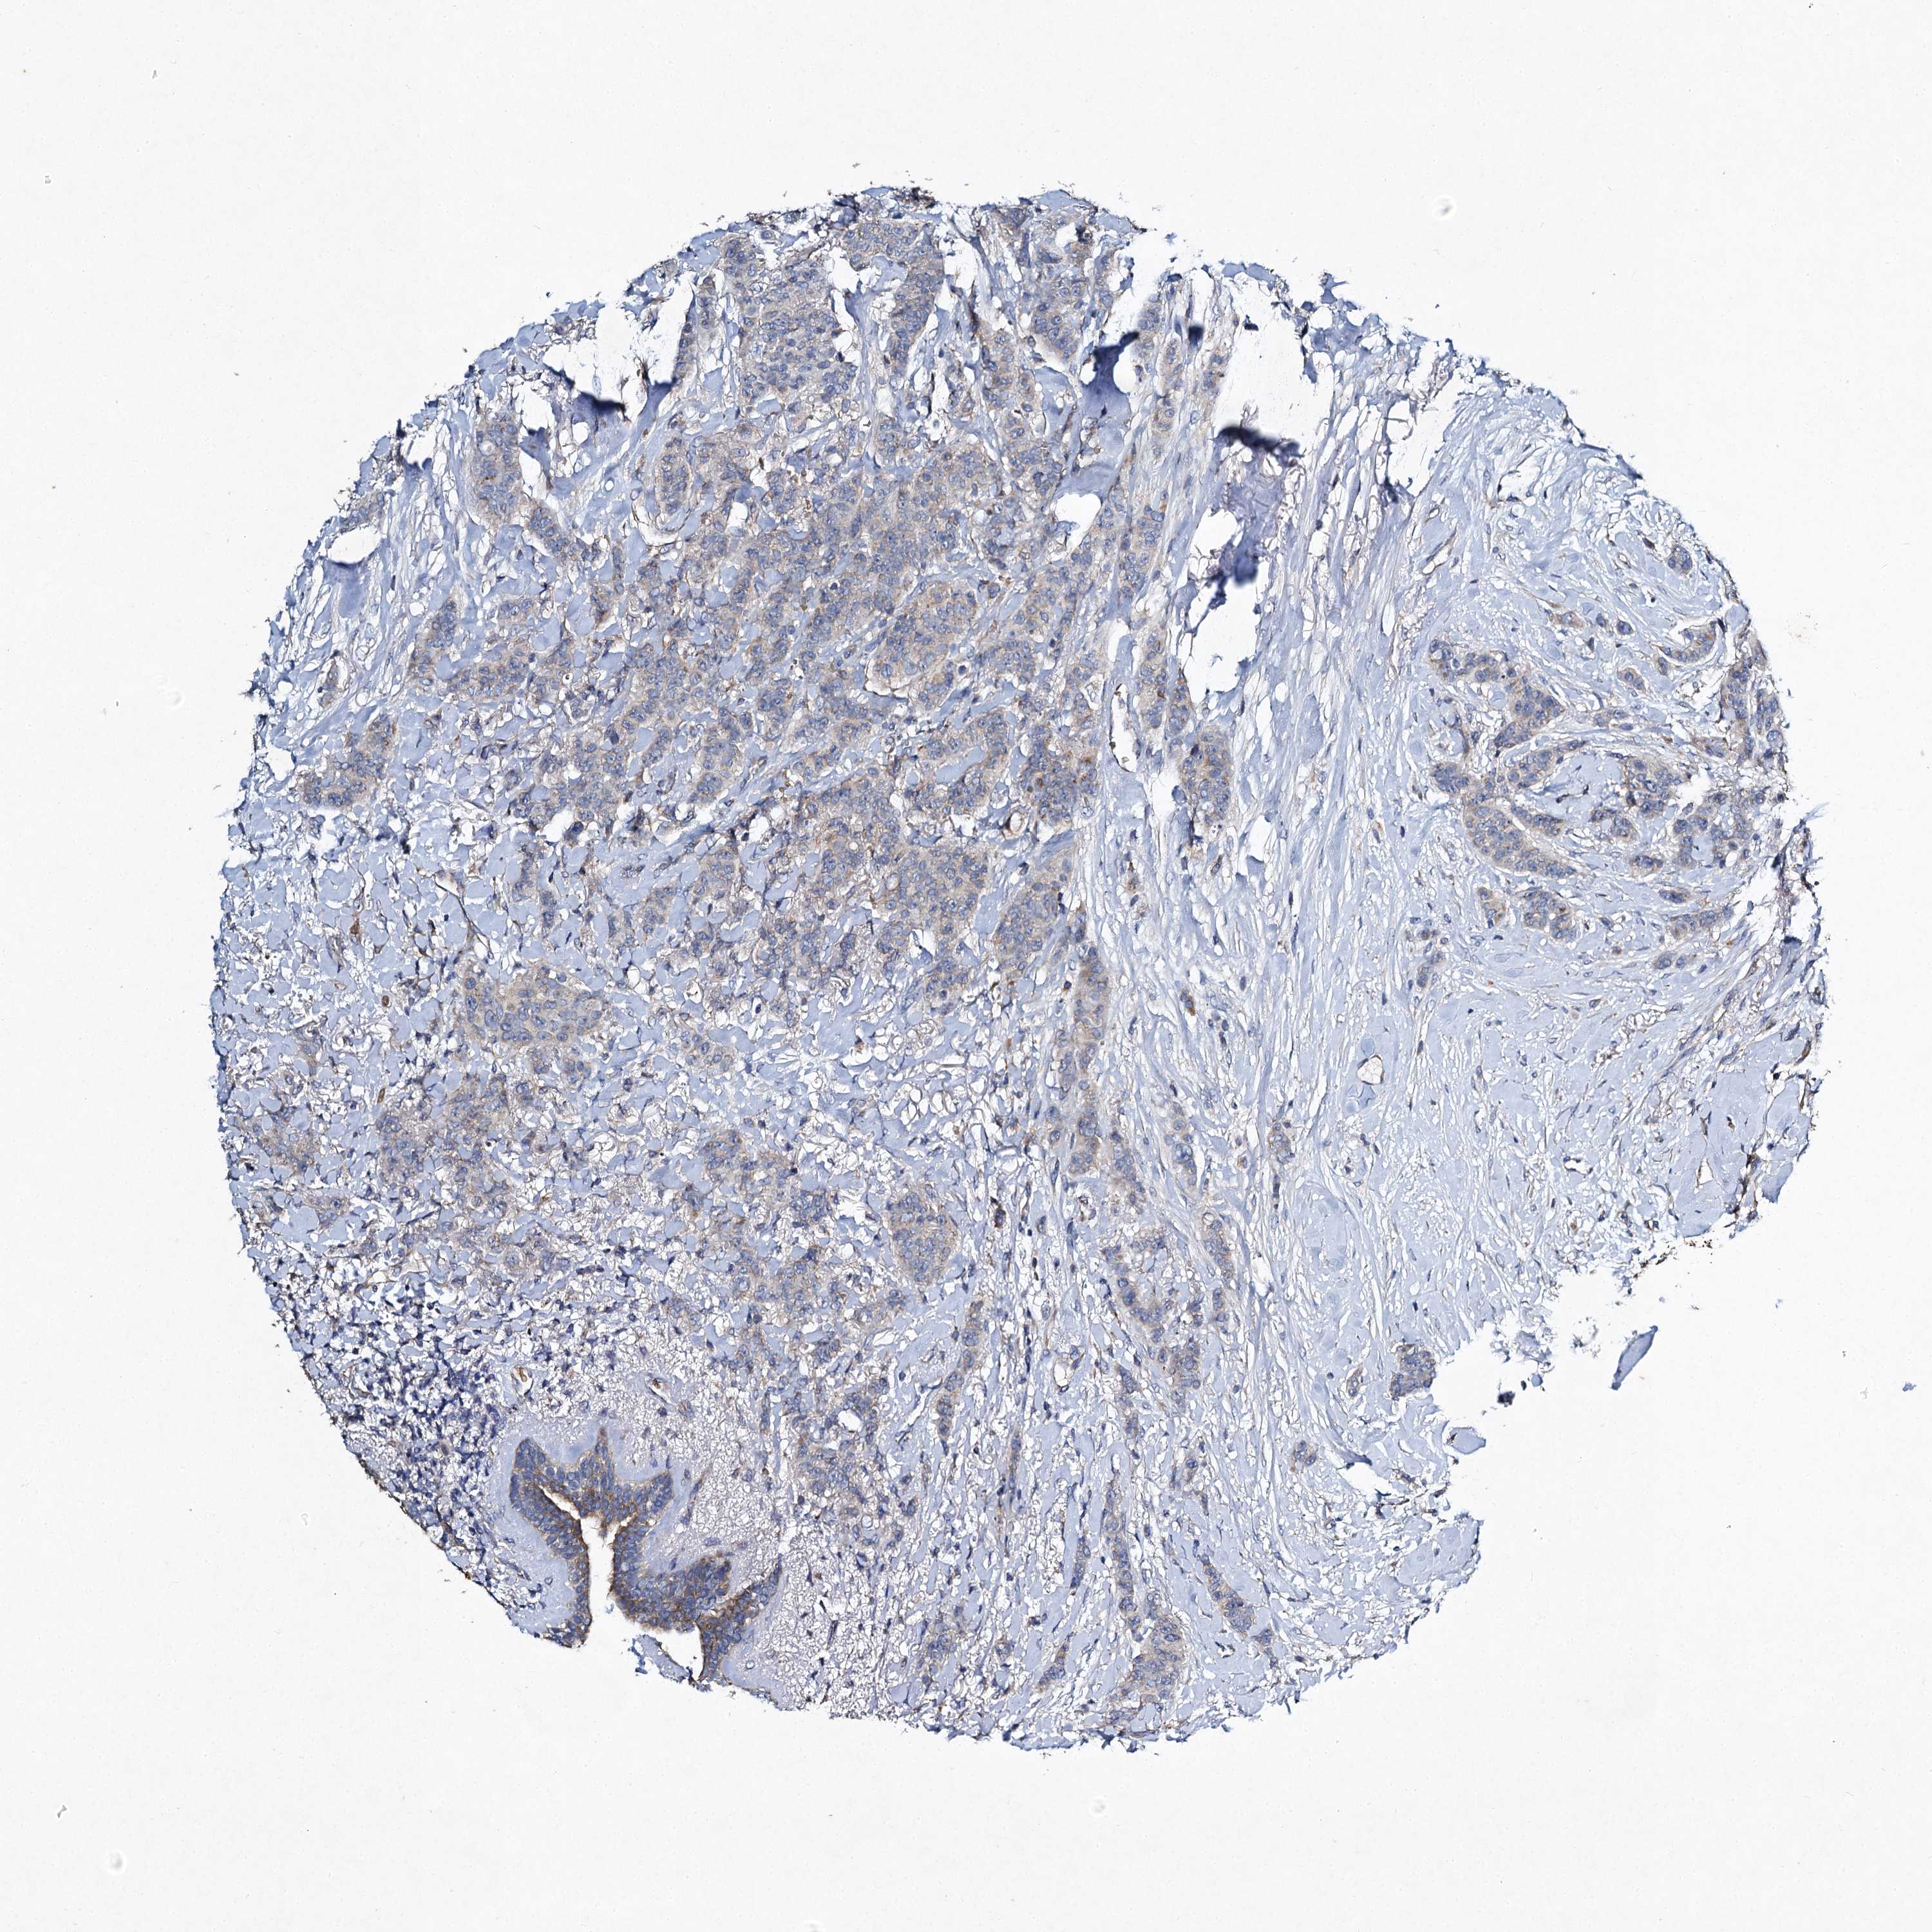

BRCA TCGA BRCA VALIDATION PROTEIN EXPRESSION